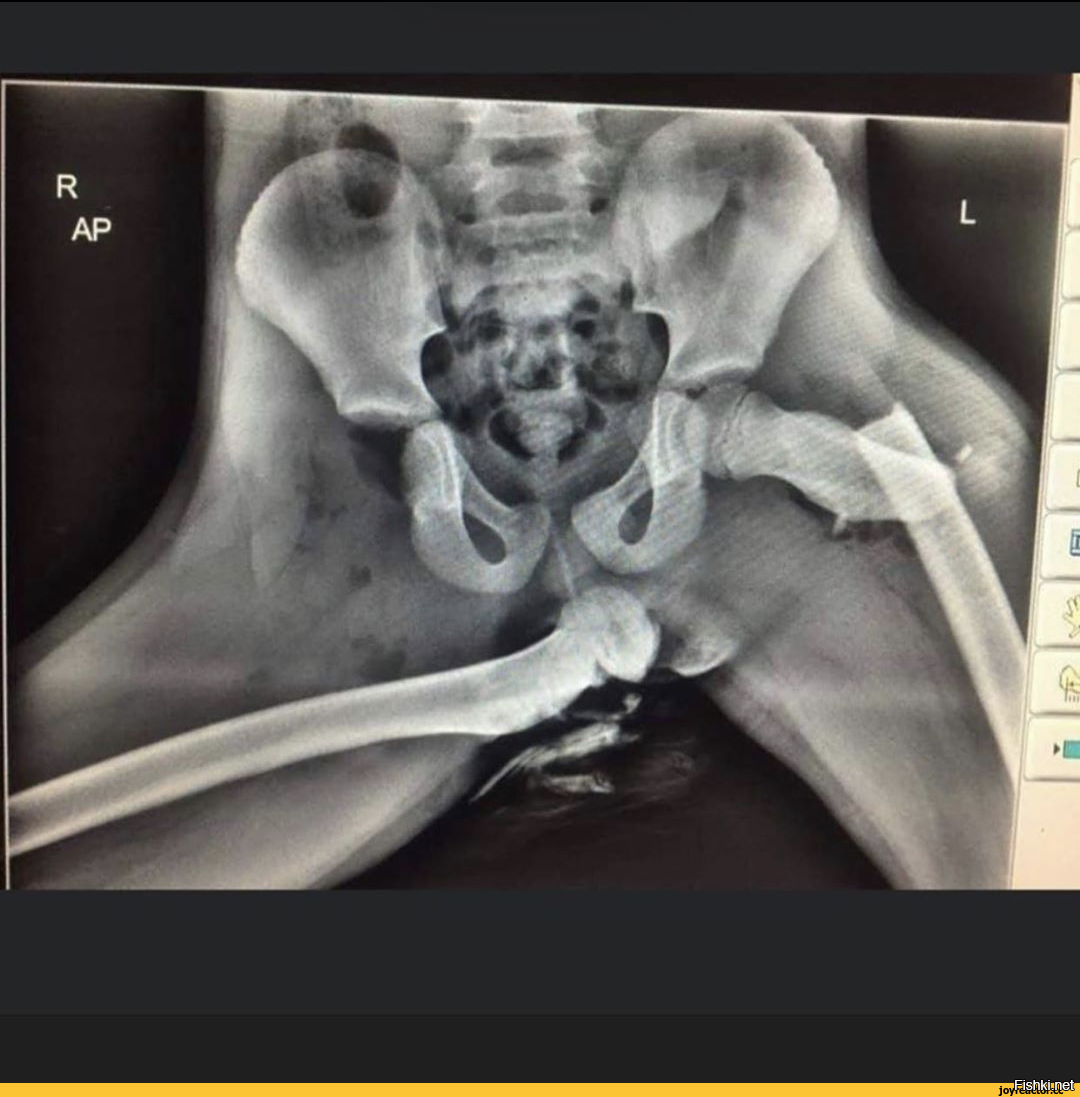

Перепутали рентген

Перепутали рентген 117 фотографий